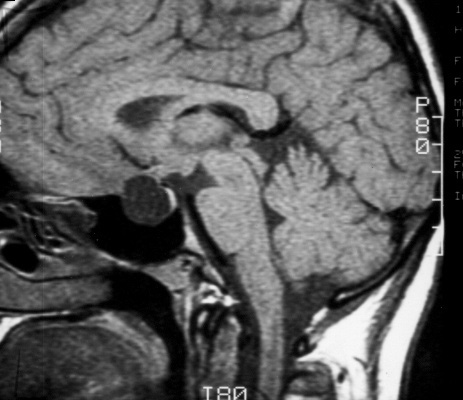

Symptomatic Rathkes cleft cysts usually present in adulthood. INH Inflammatory and infectious infundibular lesions were found exclusively in adults. In the human the intermediate lobe of the pituitary is vestigial and often includes small cystic spaces derived from the cleft. The purpose of this study was to describe the significance of intracystic nodules a diagnostic characteristic found in Rathkes cleft cysts on MR images. Postcontrast T1 sagittal MRI of 2 different patients showing small nonenhancing cyst white arrows less then 3 mm in size between the anterior and posterior pituitary gland consistent with pars intermedia cyst. Most are remnants of the craniopharyngeal Rathkes pouch and are distinct from Rathkes cleft dilation that is localized between the pars distalis and pars intermedia.

Sagittal Fspgr Bravo Image Displaying A 4 Mm Pars Intermedia Pituitary Download Scientific Diagram

Figure 4 Sagittal Enhanced T1 Weighted Image Endotext Ncbi Bookshelf